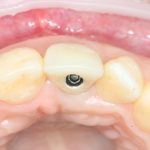

Рекомендации по установке имплантов. Для всех. Часть V.